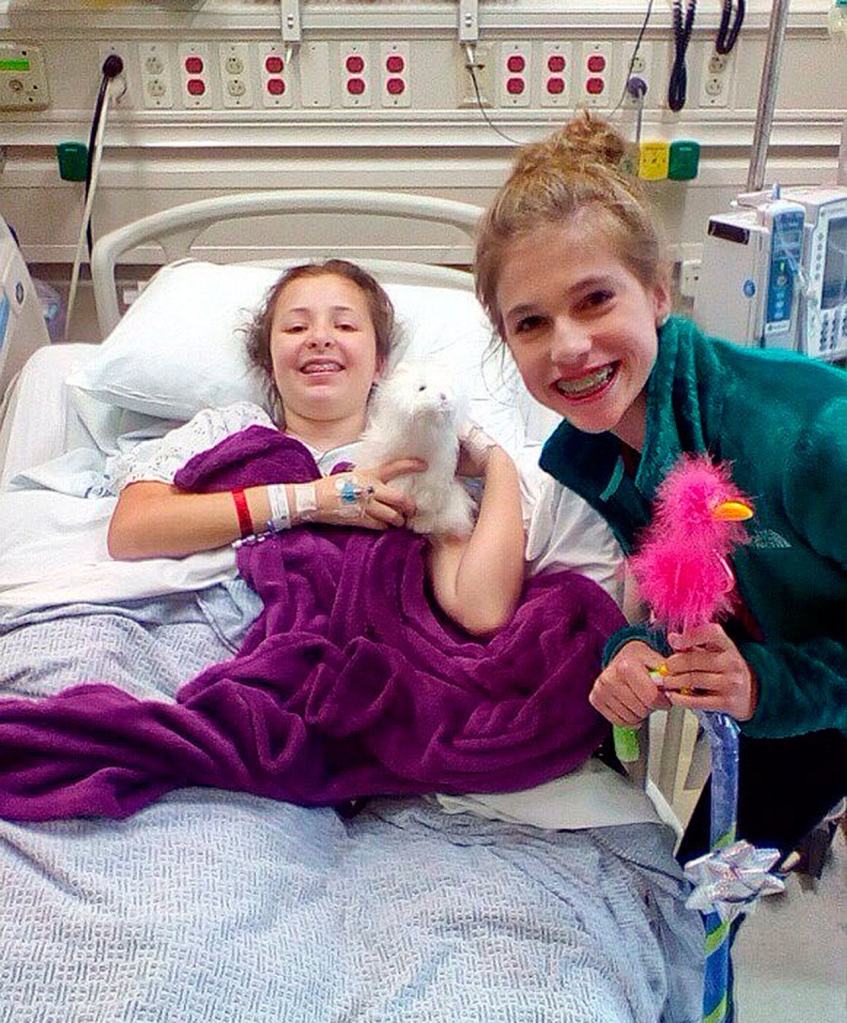

What was expected to be a routine physical for track turned into a painful 9-month ordeal for Federal Way teen Zamora Simpson this past year.

It took Simpson months to fully recover from her back surgery, which included relearning how to walk, but she’s back to her active self, swimming on Decatur’s swim team and looking forward to trying out for tennis in the spring.